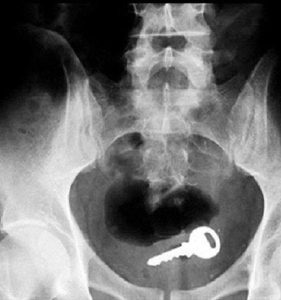

Doktora görün, tahlilleri yaptır, röntgenleri çektir falan filan derken sayılmadan yaşam gider. Gelin ki bu sefer ilginç şeyler çıkmış ki görün ağzımız açık kaldı…

Röntgen filmlerinden çıkan akıl almaz şeyler Hastane koridorlarına düşenler bilir…